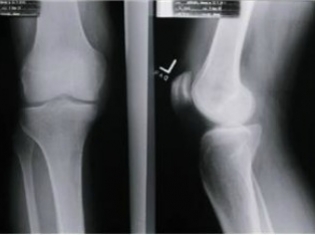

Osteoporosis is characterized by the loss of bone density. It happens when the body does not form enough new bone tissue, which makes bones brittle and prone to fracture. Osteoporosis is most common in menopausal and post-menopausal women.

Her study involved 79 premenopausal women who were abdominally obese. Thirty-two percent of the women had osteopenia – low bone mineral density that's not yet osteoporosis - and one woman had full osteoporosis.